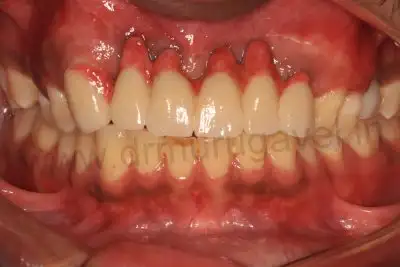

Front view of healed implants

Implants in front teeth

Side view of implants

- It should be noted that his provisional bridge had hygienic gaps in the gum region , this denotes perfect gum healing and the implants condition was confirmed after taking radiographs ( OPG & CBCT ).

- The patient was happy with esthetics and teeth shape and size of his old provisional bridge , so the same replica of this was planned to do in permanent teeth also. The permanent bridge CAD CAM zirconia was delivered in 3 days .